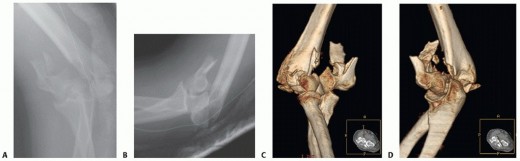

PATIENT HISTORY AND PHYSICAL FINDINGS Distal humerus fractures occur in two age groups: Younger patients who …

DEFINITION Fractures involving the proximal region of the humerus that provide the supporting framework for t…